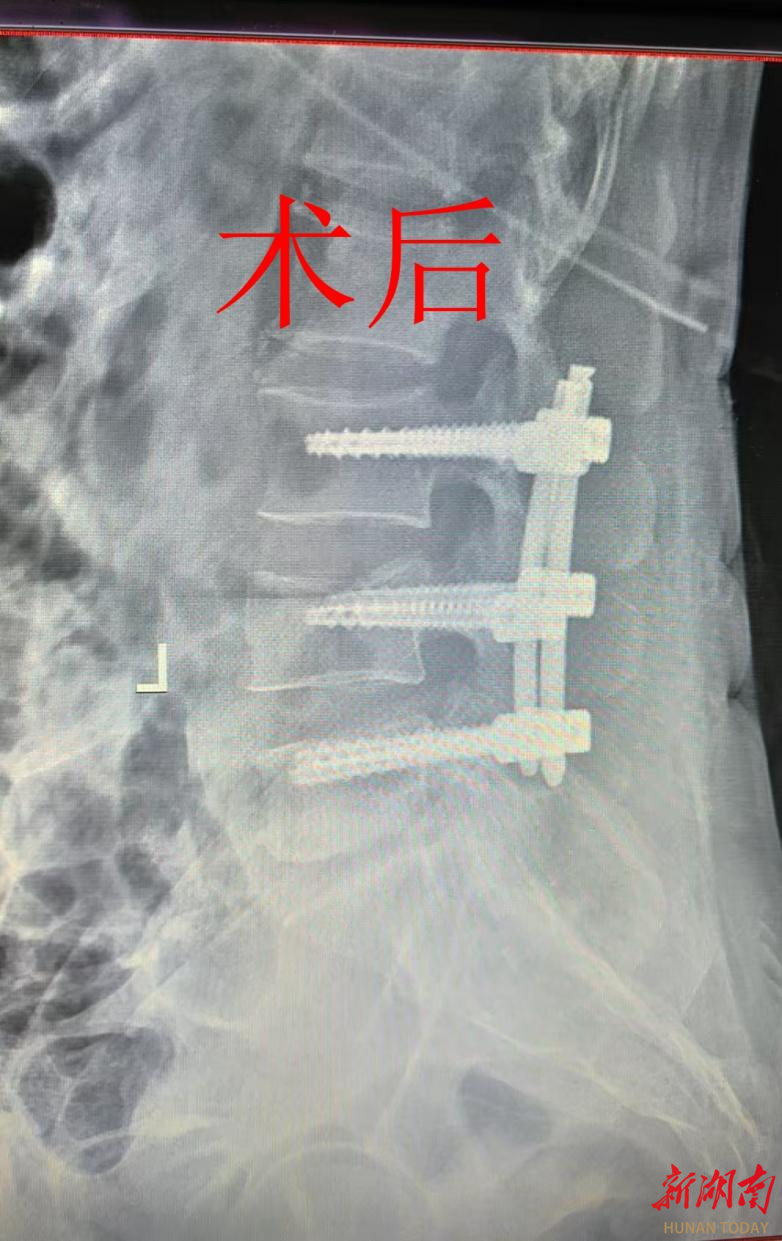

4、腰部爆裂性骨折非常严重,只有腰椎受到非常重大的损伤后才会导致爆裂性骨折一旦产生爆裂性骨折意味着椎体粉碎程度非常严重,而且会导致椎体不稳定,急需手术治疗在遭受暴力的过程中,绝大多数都会导致脊髓硬膜囊神经根等部位损伤所以一旦产生爆裂性骨折,特别常见的是骨折水平以远的不全瘫,甚至截瘫;腰骨头骨折是指腰部脊椎骨腰椎因外力作用或病理因素导致的骨结构断裂,属于脊柱损伤中较为严重的类型,需及时干预以避免神经功能损害或长期残疾症状表现腰骨头骨折的典型症状包括剧烈腰痛,尤其在受伤部位腰部活动受限,如无法弯腰转身或保持特定姿势神经压迫症状,如下肢麻木无力刺痛,甚至。